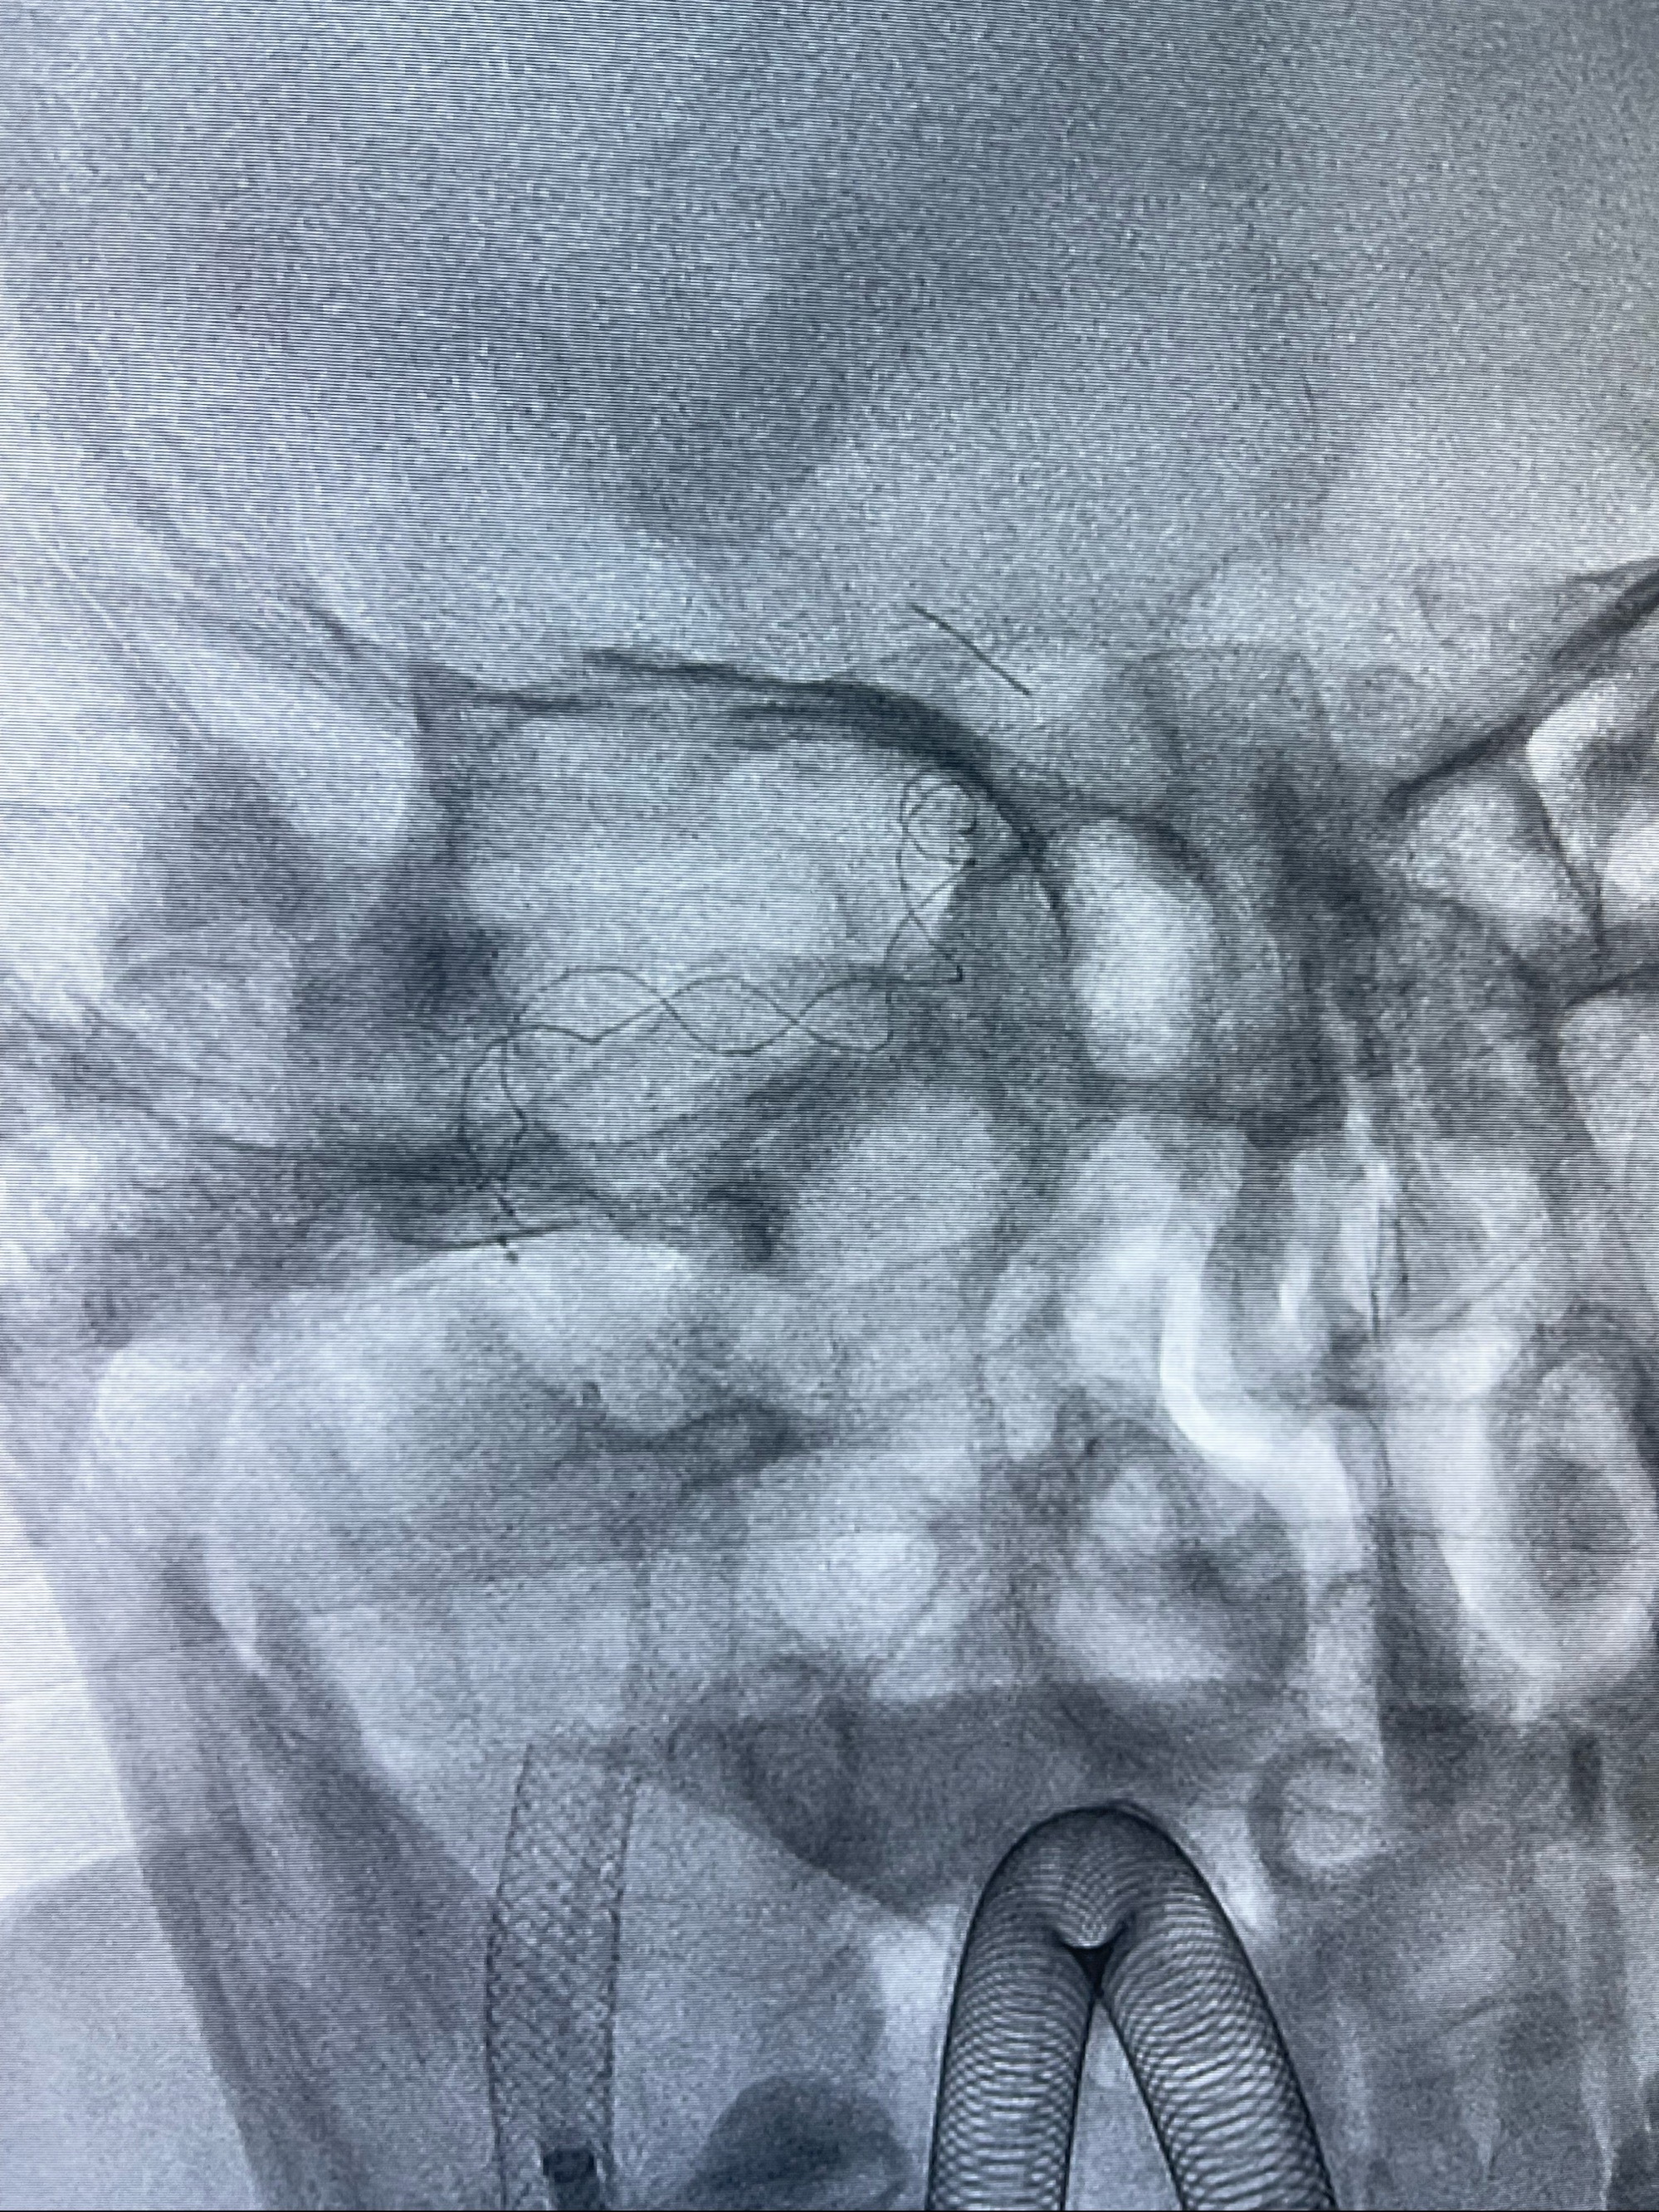

双抗准备后于2023-07-13在全麻下行右侧颈内动脉功能保护

088NeuroMAX100cm长鞘在125cmMPA及黑泥鳅导丝引导下超选择性插入右侧颈内动脉支架内

经导引导管造影显示支架远端颈内动脉不规则狭窄伴局部充盈缺损,同时行全身肝素化5ml

路径图下4-20mm球囊在导丝引导下超选择性至狭窄段,以6-8个大气压扩张,持续30s

泄除球囊造影显示局部管腔扩张佳

后移球囊至颈段狭窄段,以8-12个大气压扩张,持续30s后泄除球囊

即刻造影显示狭窄扩张佳

重新行“路径图”,支架导管在微导丝引导下超选择性插入至右侧颈内动脉眼段,4.5-50mmLeo支架释放,远心端位于海绵窦段,近心端位于岩骨段狭窄段以近

即刻造影显示支架贴壁佳

路径图下,5.5-50mmLeo支架导管在微导丝引导下超选择性插入远段Leo支架内

两枚支架部分重叠

多次确认支架位置及打开贴壁情况

支架完全打开,近心端位于原颈动脉支架远心端内